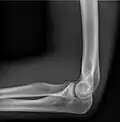

- Elbow - AP and Lateral. Radial head projections available on request

-

Lateral projection -

Anteroposterior projection -

Left elbow by 30 degrees internal oblique projection -

Left elbow by 30 degrees external oblique projection